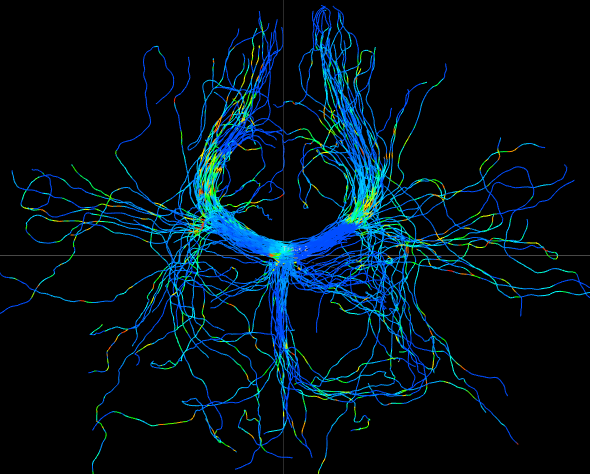

We perform whole brain streamline tractography on the estimated fODF field using mrtrix (Tournier et al., 2012) 888http://www.mrtrix.org/. The voxels with GFA larger than are used as seed voxels to generate tracts by using tckgen in mrtrix. All other parameters are default parameters in mrtrix. The obtained fiber tracts are then visualized by using trackvis 999http://trackvis.org. Fig. 14 and 15 demonstrate the tracts respectively cross two given ball ROIs. The tracts are colored by using the proposed six scalar indices. Note that the proposed scalar indices are calculated based on estimated fODFs, not based on fiber tracts. It can be seen that 1) OO is high in areas with well aligned fibers, while OD is high in crossing areas and distortion areas; 2) distortion indices are low when fibers are well aligned; 3) the total distortion index is high in areas with highly curved fibers or crossing fibers. 4) although splay, bend, twist indices may be separable (e.g., one is large while another one is close to zero) in synthetic data, in real data, these three types of distortions normally occur together, especially for bending and splaying. 5) the ROI in Fig. 14 is the crossing area of the Corpus Callosum and the Fornix, where all distortion indices have high values, especially for twist and total distortion indices. This finding agrees with Fig. 12.

ROI on OO map

OO

OD

total distortion

splay

bend

twist